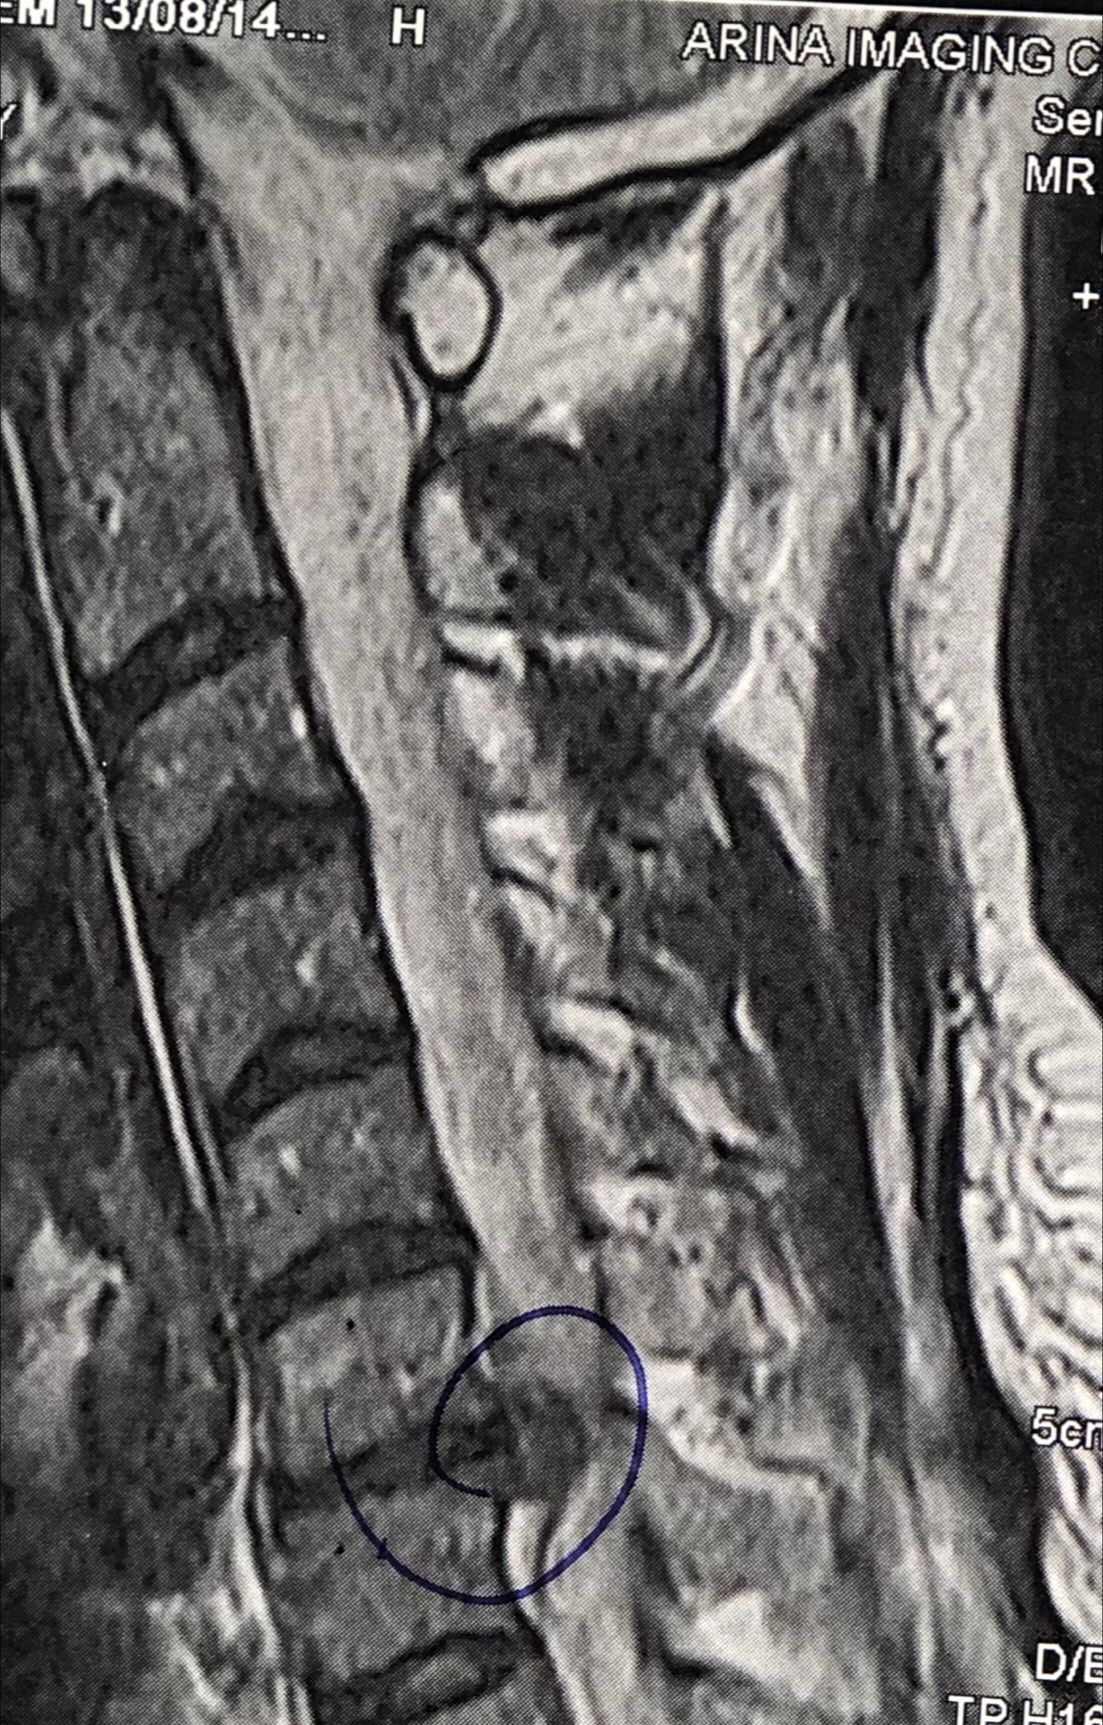

41 years old man presented to my clinic in October 2023 with acute and sever R neck pain with radicular pain to his R upper extremity along C6 dematom since 2 weeks ago. Examination didn’t show any upper motor signs. Was suggested urgent surgery

I ordered EMG/ NCV : showed mild R C6, C7 irritation without any active axonal loss

In his MRI was reported R. para R. IVF Massive extrusion. I decided to control his pain and manage this patient with reevaluation of patient every other session. For 5 sessions i just used acupuncture and laser and IFC and mild adjustments to his R. T3-T7 and mild arthosteem to above and below involved segment. Cervical adjustment considered contraindicated for this patient. From session 6th- 8th i started to use mild/gentle cervical decompression. He used soft cervical collar all the time. His pain decreased by 80 percent

I gave him cervical traction pump to be used 3-5 times per day at home for the next 3 months and i released the patient. He was evaluated every week once for one month and after that every 2 weeks. After 3 month I repeated MRI. Size of the herniated disc was reduced greater than 50 percent. Asked him to do another mri in 6 months

In general: Precise selection of the patients, examination,diagnosis, plan of management, reevaluation and treatment can be done by doctors of chiropractic for the patients with spinal disc herniation and stenosis Moreover giving reasonable time to these kind of patients under direct supervision by their chiropractic doctors can prevent unnecessary surgery. Proper selection of these kind of patients is another important fact that can be done precisely by chiropractors.

MRIs before and after proper management of this patient: